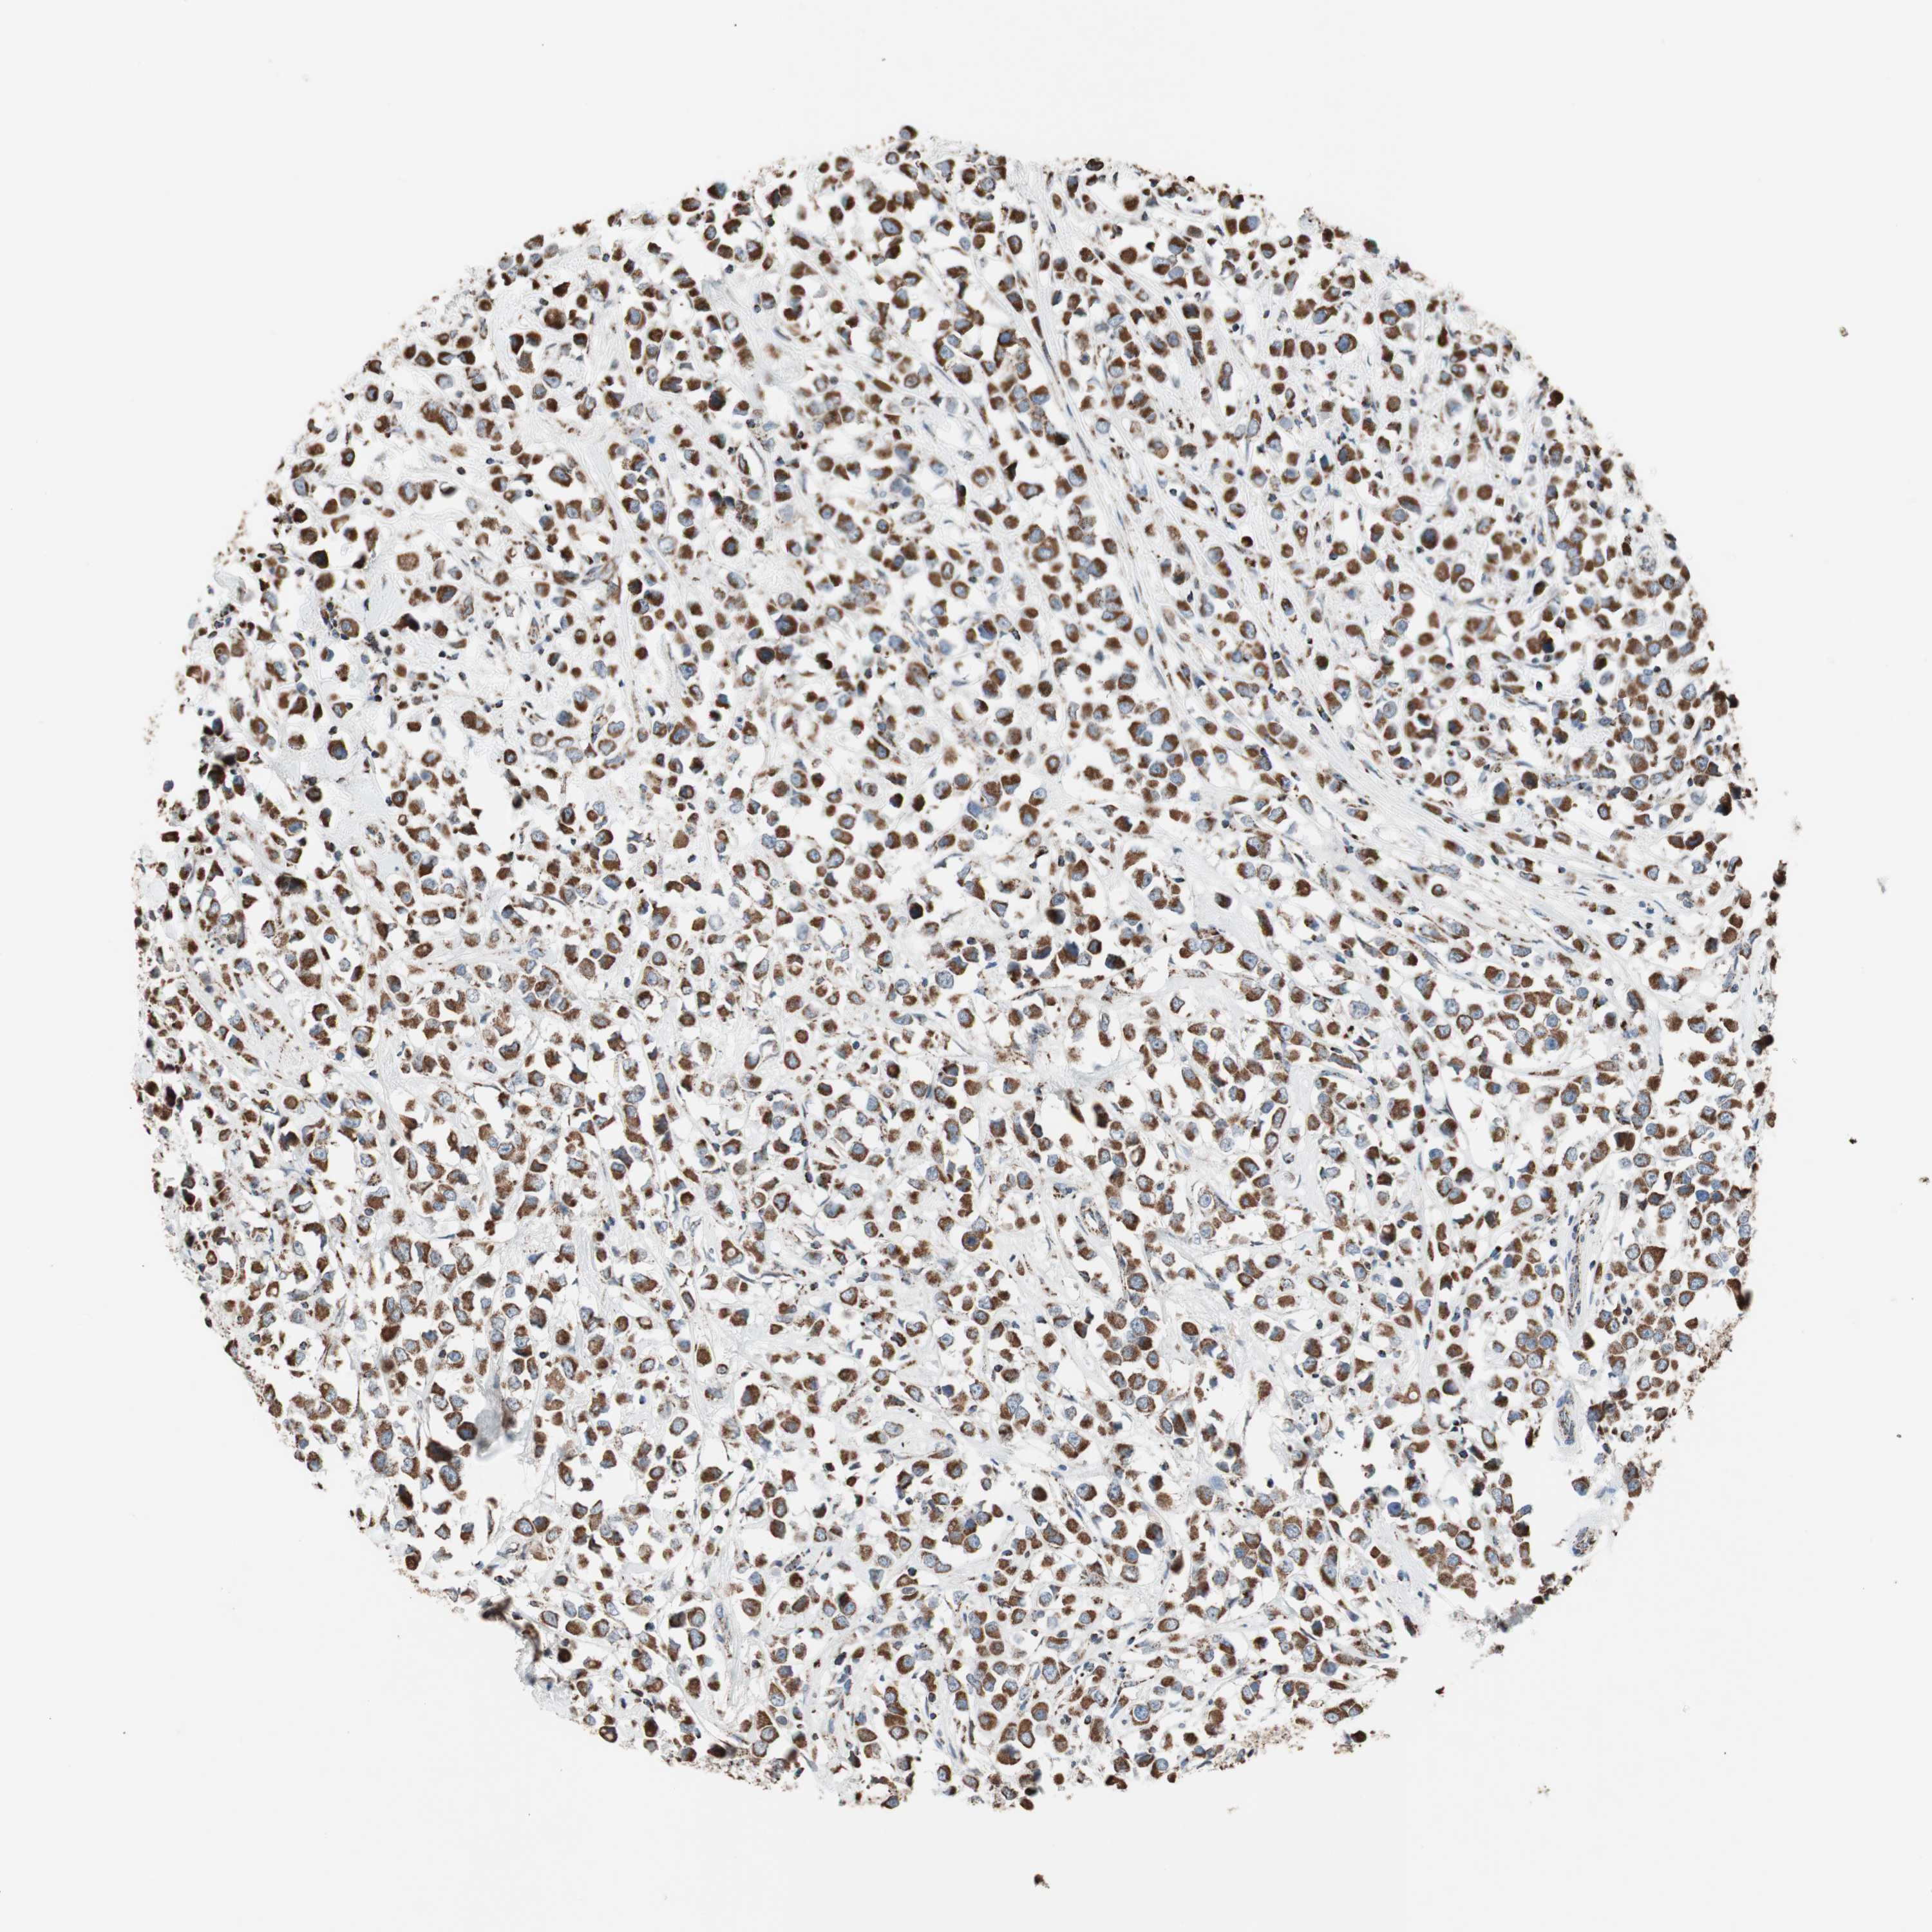

CANCER BREAST CANCER Show tissue menu

BRCA TCGA BRCA VALIDATION PROTEIN EXPRESSION

ANTIBODIES

AND

VALIDATION